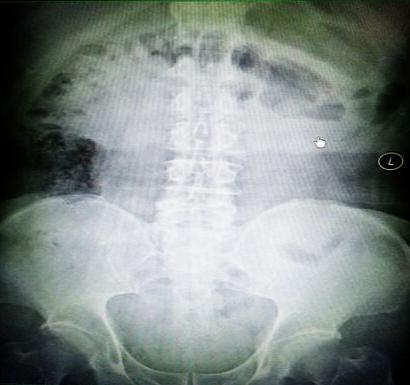

受試患者在結(jié)腸端端吻合術(shù)中,使用我司新研制產(chǎn)品達(dá)到了理想的預(yù)期效果?;颊咝g(shù)后7天、14天X光片顯影,可降解腸道支架均能按研制設(shè)計(jì)的預(yù)期時(shí)間節(jié)點(diǎn)保持應(yīng)有強(qiáng)度,術(shù)后21天X光片顯示可降解腸道支架已完全破碎,并排出體外。在整個(gè)試驗(yàn)過程中,病患無任何不良反映,耐受良好。